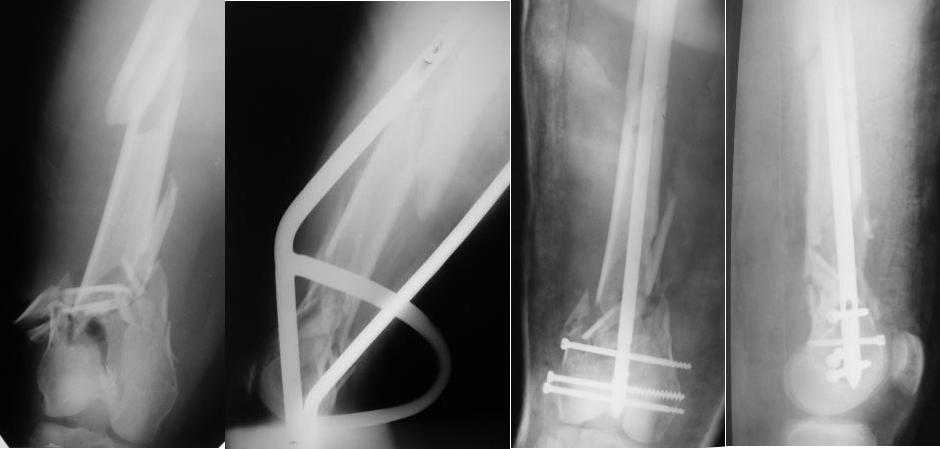

Re: Многооскольчатый перелом бедра

Приносим извенения за недостаток информации. Выкладываю все снимки. Стержень фирмы НПО ДЕОСТ(г.Пущино-на-оке)